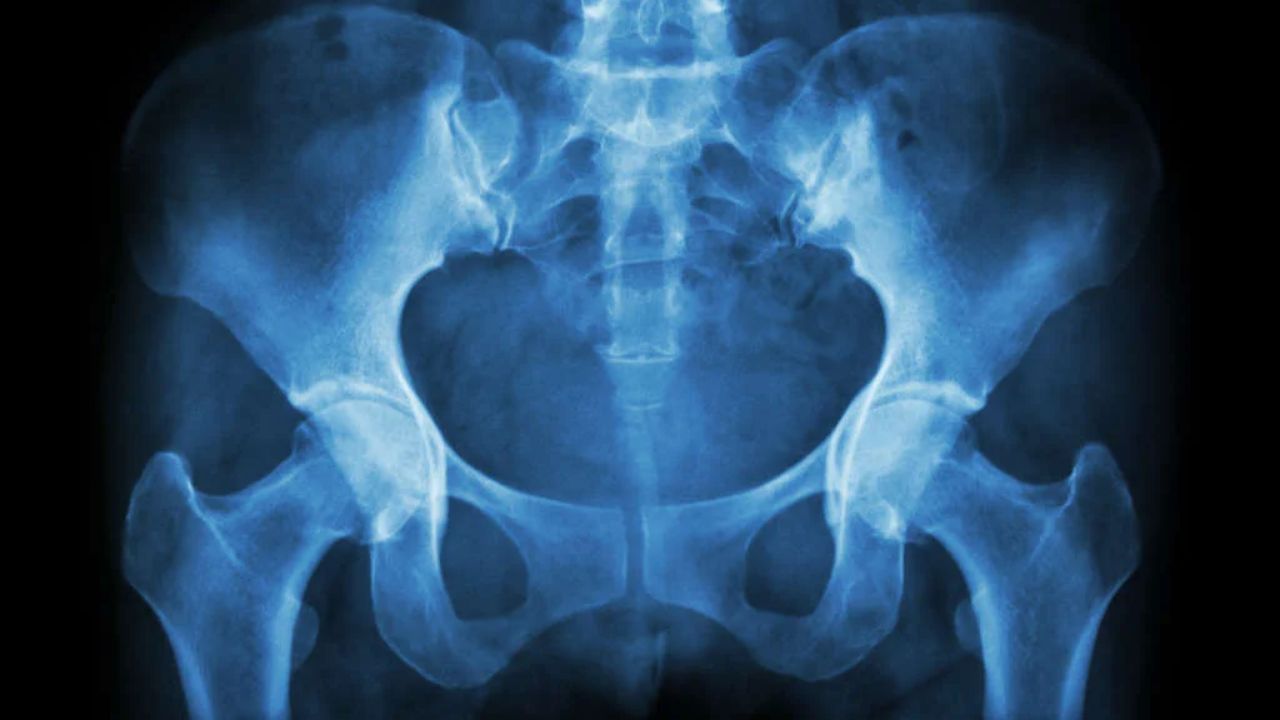

Exames e avaliação ortopédica O ortopedista realiza um exame clínico dinâmico, reproduzindo o movimento que gera o estalo para identificar a estrutura afetada. A ultrassonografia dinâmica é excelente para visualizar o tendão saltando em tempo real, enquanto a ressonância magnética é fundamental para investigar lesões internas na articulação, como rupturas labrais, e descartar outras patologias ósseas.